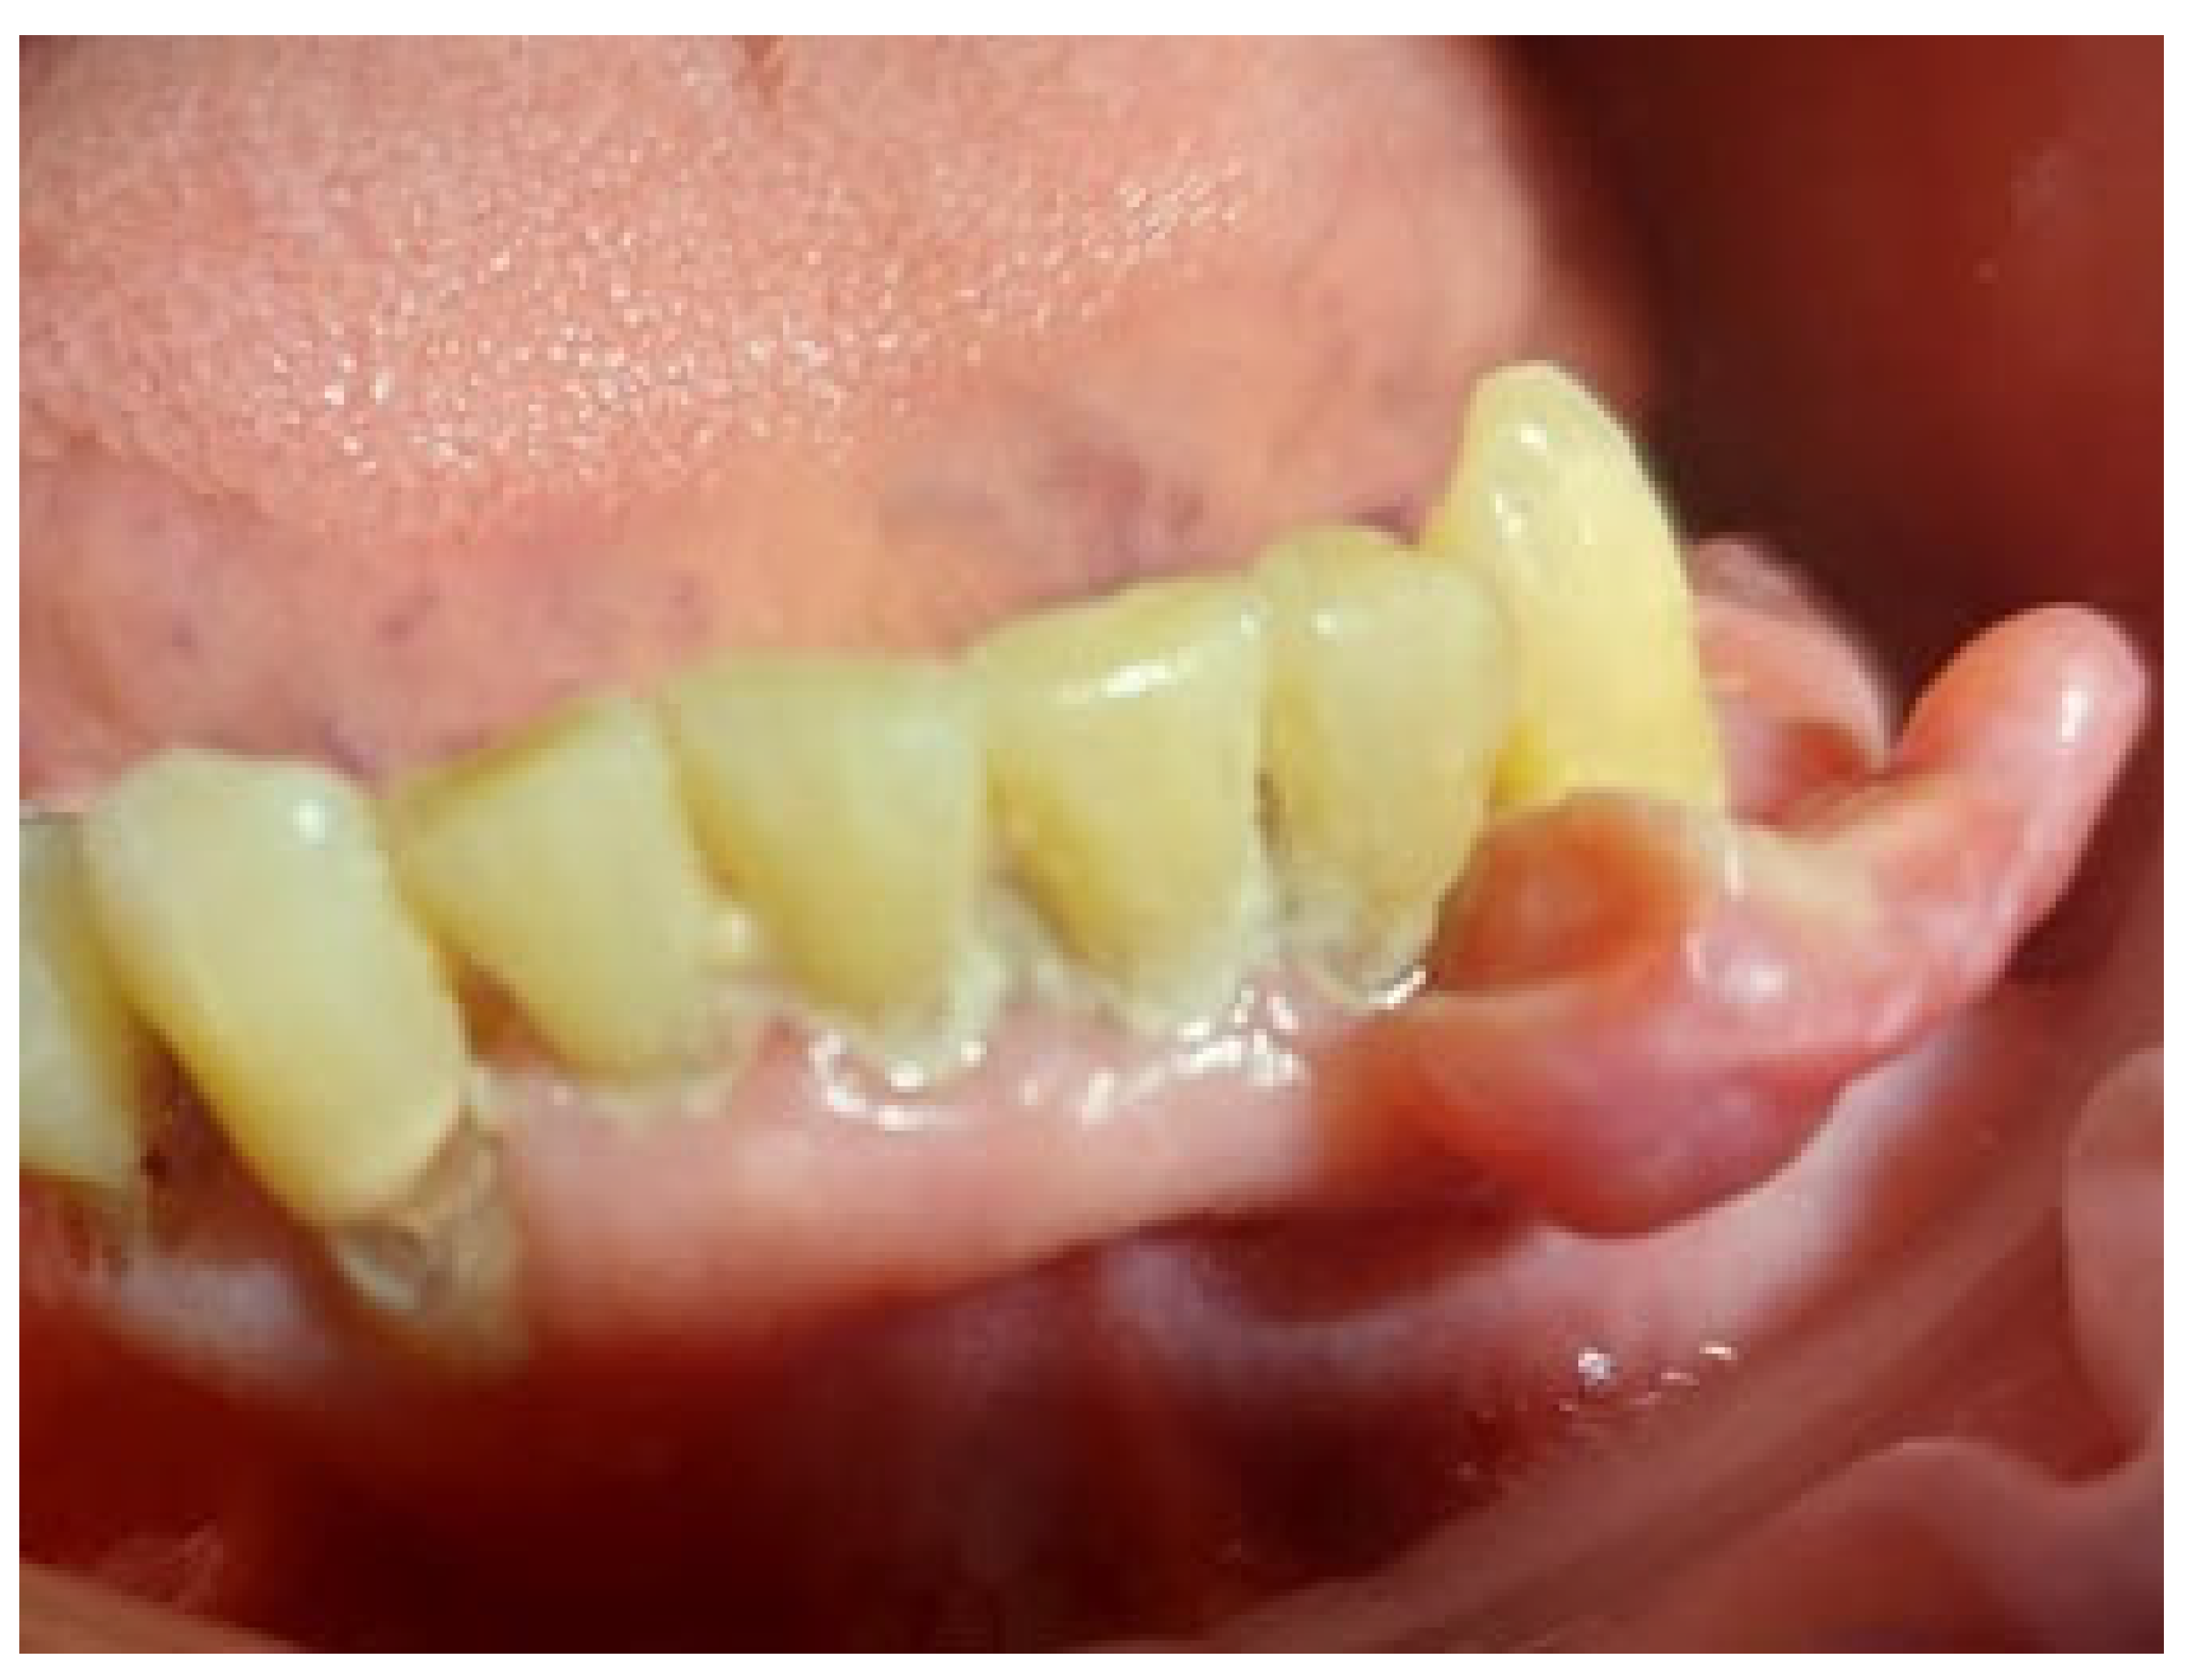

On the day of presentation to the Department of Oral Surgery, the extraoral examination noted painless, enlarged submandibular lymph nodes on the left side. Intraoral examination revealed the presence of gingival tumors in the area of teeth 17-16 (Figure 1a) and 32-33 (Figure 2 and Figure 3). The lesions were pedunculated, with a narrow pedicle, elastic-hard, irregularly elliptical in shape with impressions of adjacent teeth, pink in color with local hyperemia and white spots. They arose from the marginal gingiva, which was swollen and protruding. The patient had active periodontal disease. The maxillary tumor measured 22 x 10 x 5 mm, the mandibular tumor 30 x 20 x 6 mm and was in close proximity to the teeth. The periodontium was inflamed with the presence of pathological pockets and plaque deposits. Teeth 17, 16, 33 showed grade II mobility. Residual roots of teeth 34, 35 were present. The panoramic radiograph did not show any abnormalities in the bone structure of the tumor area. The patient underwent professional hygiene before surgical treatment due to abundant plaque deposits. Clinically, the image corresponded to reactive hyperplastic lesions, resembling fibrous hyperplasia or pyogenic granuloma.

Figure 3. Mandibular tumor in the area of teeth 32-33.